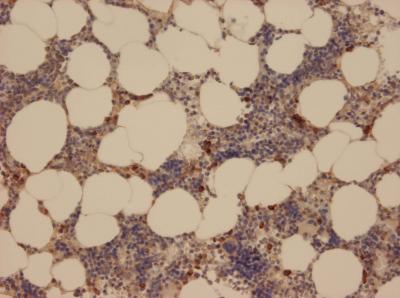

Neutrophil granulocytes comprise important defences for the immune system. When pathogenic bacteria penetrate the body, they are the first on the scene to mobilise other immune cells via signal molecules, thereby containing the risk. To this end, they release serine proteases – enzymes that cut up other proteins to activate signal molecules. Scientists at the Max Planck Institute of Neurobiology in Martinsried have now discovered a new serine protease: neutrophil serine protease 4, or NSP4. This enzyme could provide a new target for the treatment of diseases that involve an overactive immune system, such as rheumatoid arthritis.

The functioning of the immune system is based on the complex interplay of the most diverse cells and mediators. For example, neutrophil granulocytes (a group of specialized white blood cells) react to bacteria by releasing substances called serine proteases. These enzymes are able to activate signal molecules, such as the chemokines, by cleaving them at a specific position on the molecule. The active signal molecules then guide other immune cells to the focus of inflammation in order to destroy the pathogens.

The fact that the enzyme remained undiscovered until now is because it occurs at a much lower concentration than the other three proteases. The Max Planck scientists came across it while searching the human genome for genes that encode serine proteases. In the process, they noticed a previously unknown gene sequence. Natascha C. Perera, a member of the Martinsried research group and lead author of the study, managed to produce and examine the enzyme in its active, folded state.